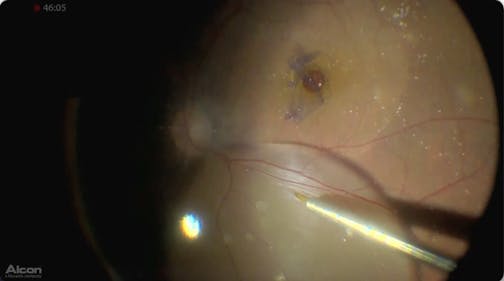

Myopic Macularschisis

Ehab El Rayes, MD